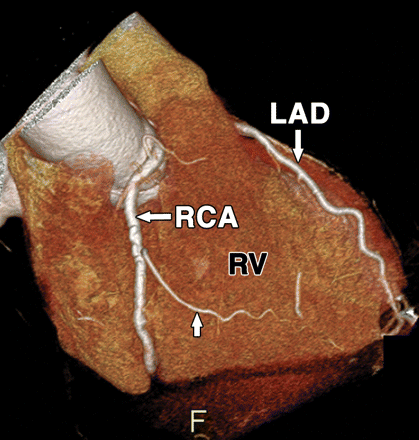

Coronary artery origin anomalies are more common with BCAV. We also know co-arctation of aorta has a embryological link with BCAV.

The coronary artery origin anomalies are common